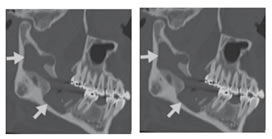

Figure 8: Keratocystic odontogenic tumor. (A) Oblique sagittal CT image demonstrates large radiolucent mass (arrows) in posterior body of mandibular ramus, with scalloping of cortex. (B) Axial contrast-enhanced CT image demonstrates cystic mass with mild peripheral enhancement (arrow) breaking through cortex and extending into left masseter muscle.

8